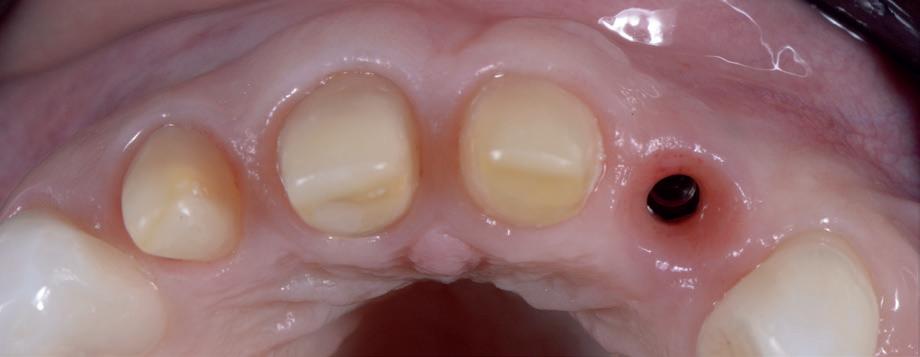

Dit membraan kan direct na extractie gebruikt worden bij een ridge preservation procedure, waarbij het membraan gedeeltelijk onbedekt blijft. De weefsels worden met opzet niet primair gesloten, vandaar dat wij dit vanuit onderwijs oogpunt “open GBR” zijn gaan noemen aangezien veel collega’s het beeld hadden/hebben dat de weefsels altijd primair gesloten dienen te worden bij deze procedure. Een voordeel hiervan is dat er geen tweede chirurgie nodig is om het membraan te verwijderen. Deze membranen kunnen ook gebruikt worden wanneer er te weinig bot aanwezig is om te implanteren, maar waarbij de elementen al in een eerder stadium verwijderd zijn. Bij dergelijk defecten is het van belang om het weefsel wel volledig primair te sluiten en noemen wij dit voor de duidelijkheid “gesloten GBR”.

34 MEMBRANEN

In het geval van “open GBR” direct na extractie hoeft de wond dus niet gesloten worden. Zo kan er (nieuw) gekeratiniseerd weefsel worden gecreëerd. Dit komt ten gunste van de breedte van de uiteindelijke hoeveelheid gekeratiniseerde weefsel rondom de hals van het toekomstige abutment, zodat ook de stabiliteit en reinigbaarheid van de suprastructuur verbetert.

Zes maanden na extractie wordt het implantaat 37 geplaatst. Er is sprake van een goede genezing en de processushoogte en -breedte zijn behouden en opgebouwd. Ook is er zichtbaar gekeratiniseerd weefsel

gewonnen. De wond kan na het plaatsen van een healing abutment primair gesloten worden (Afbeelding 3a-3d).

In afbeeldingen 4a-c is het resultaat drie maanden na het plaatsen van het implantaat te zien. De genezing is volledig en de verwijzer kan de suprastructuur vervaardigen (afbeelding 4a-4c).